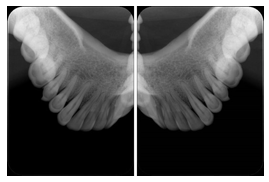

2. A patient requests cosmetic surgery to enhance their facial appearance. The case requires consultation between an orthodontist in New York and an oral surgeon in California. The cephalometric series of 2D projections constructed from a volumetric CT data set that is used for the discussion is arranged by a Structured Display for transfer between the two practitioners.

Cephalometric Series Structured Display

Figure OO-2. Cephalometric Series Structured Display